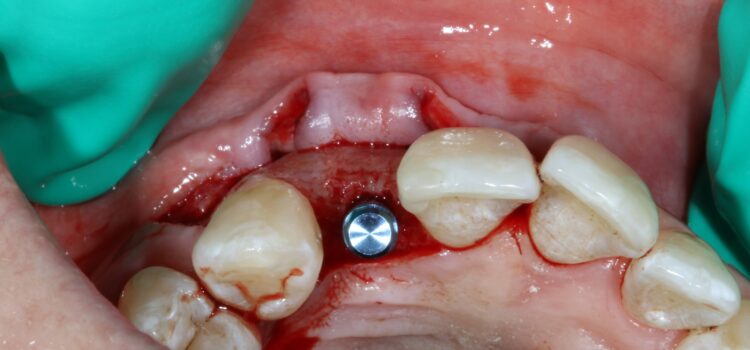

The second surgery involved a palatal crestal incision and a full thickness flap elevation revealing good turnover of bone graft into host bone. A bone level implant was placed in an appropriate three-dimensional position completely surrounded by new bone and no additional bone grafting was required. A 4mm healing cap was placed.

A free gingival graft was taken from the palate below the upper right molar teeth and the epithelium was removed on the surgical table. The connective tissue strip of graft was then placed on top of the healing cap (and suspended over the healing cap) and secured to the palatal flap with 6.0 PGA Resorba Sutures. Finally, the buccal flap was closed with complete primary intention wound healing using 6.0 Prolene.